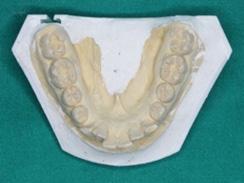

Fig. 4-E: Pre-treatment, MN occlusal view

Fig. 4-D: Pre-treatment, MX occlusal view